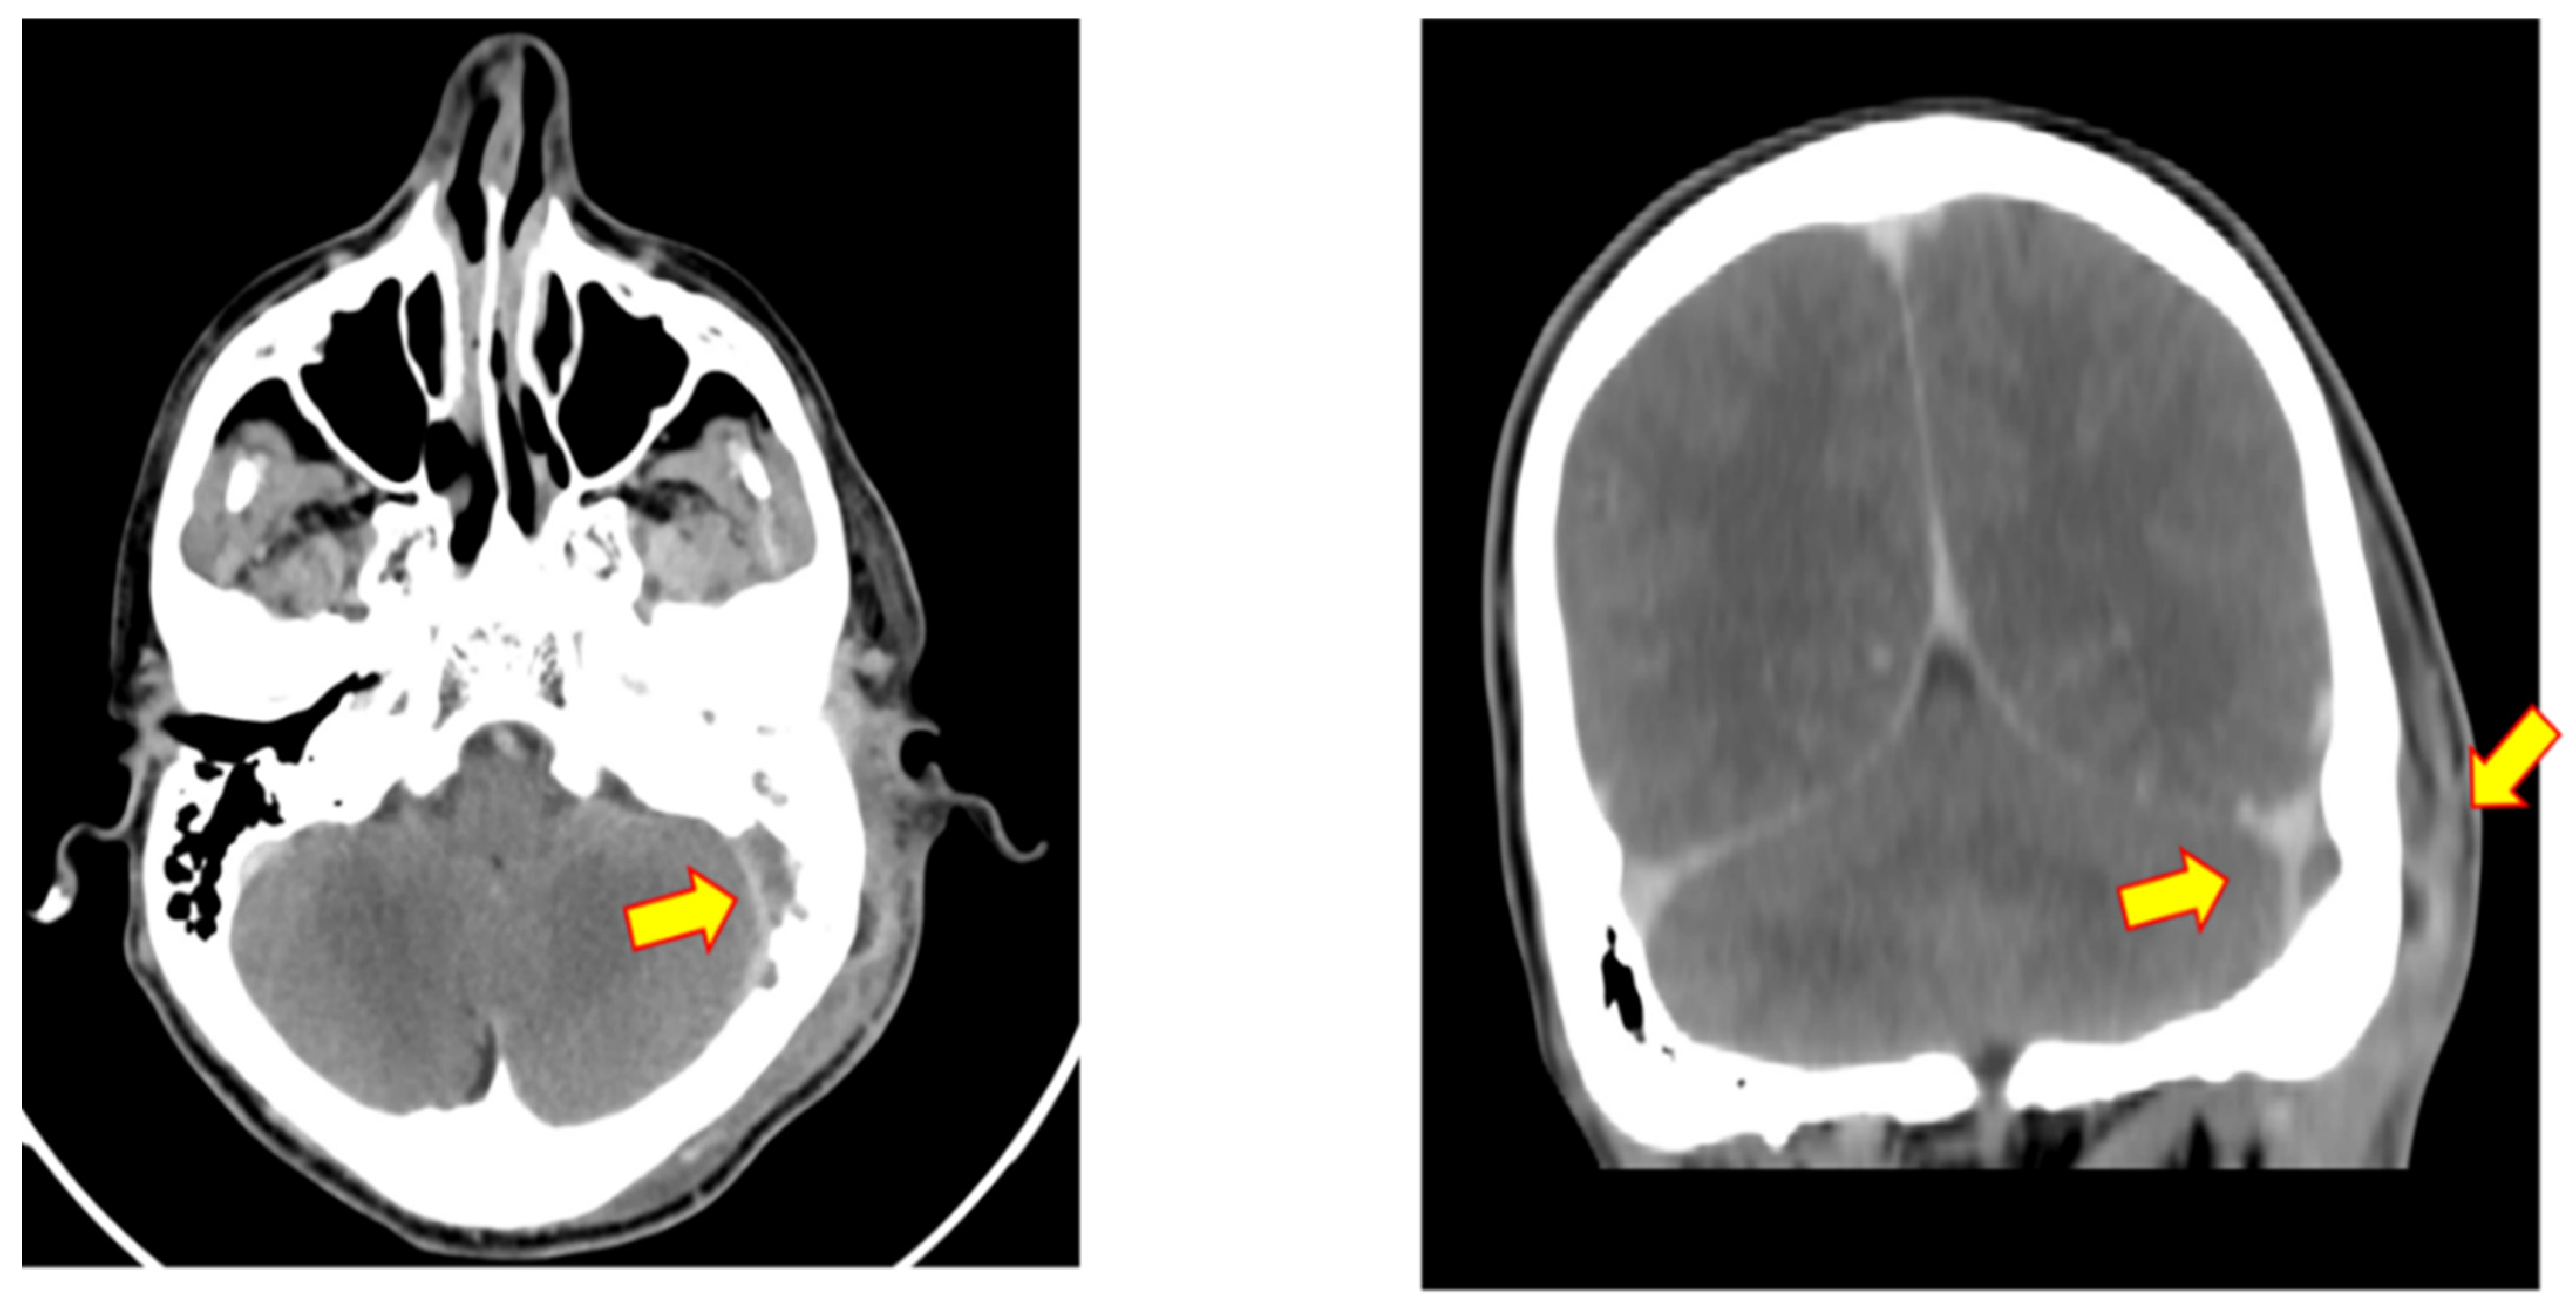

3.1. Case 1

| 18 | 2016 | Israel | Present study | 48 | m | otitis media with effusion | 1 | - | fibrous tissue with storiform fibrosis, lymphoplasmacytic infiltration, obliterative phlebitis | IgG4 positive 15 per HPF; IgG4:IgG < 20% | 210 mg/dL |